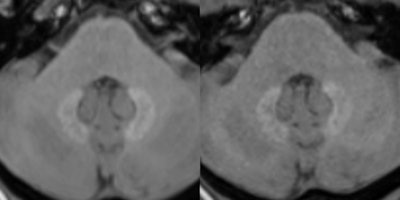

Several retrospective studies over the past several years have found that patients who received repeated administrations of gadolinium contrast had increased signal intensity in areas of their brains on unenhanced T1-weighted MR images, long after they underwent MRI scans. While the locations of the signal intensities have varied, the dentate nucleus has received much attention, in part because it is key to the body's central nervous system.

In fact, Radbruch et al published a 2015 study that found greater signal intensity in the dentate nucleus and globus pallidus among patients who received the linear GBCA gadopentetate dimeglumine. There was no such escalation in patients who had received the macrocyclic GBCA gadoterate meglumine, despite the fact that a substantially larger dose of contrast was used in the latter group.

Radbruch and colleagues found a statistically significant increase in the dentate nucleus-pons signal ratio on unenhanced T1-weighted MR images after serial administrations of the linear GBCA; however, the ratio declined in the same patients who proceeded to receive subsequent injections of the two macrocyclic GBCAs.